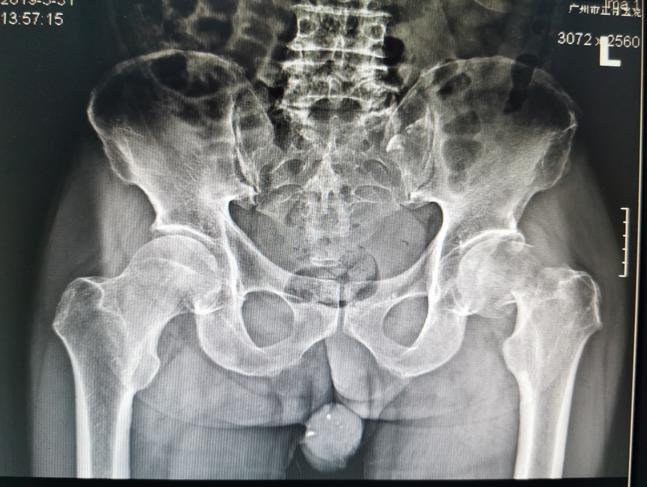

股骨颈骨折术后